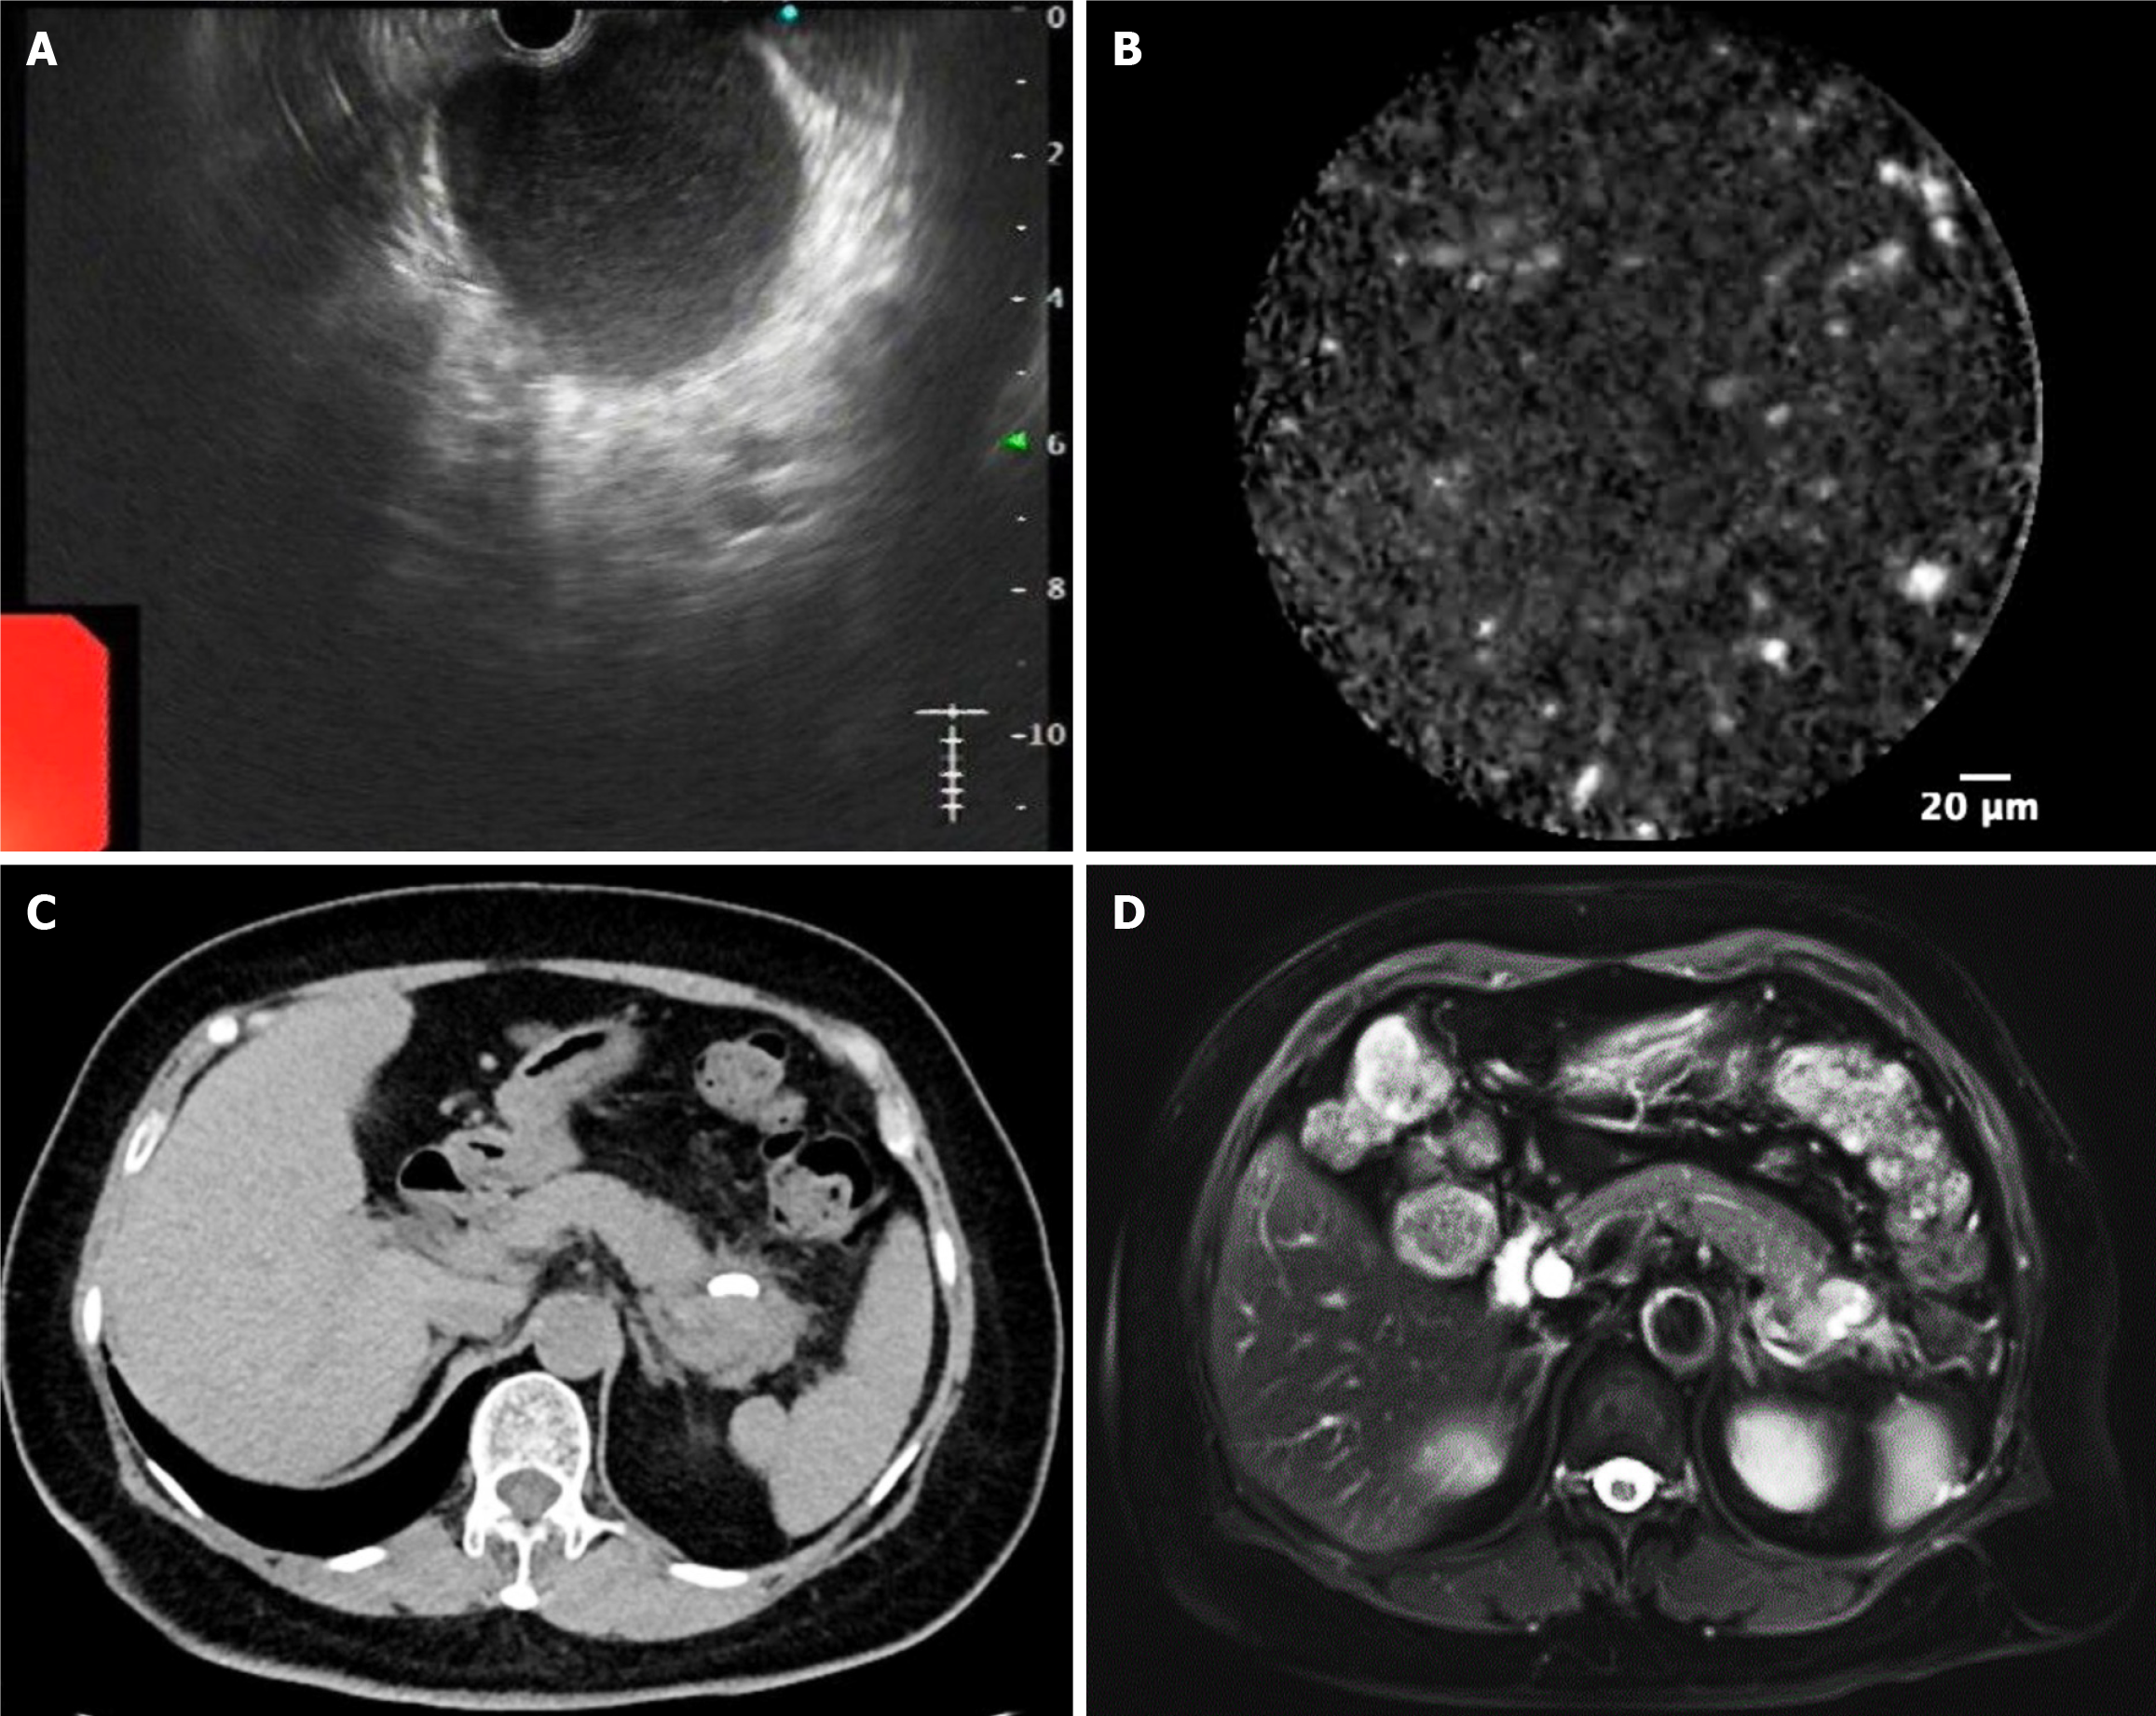

Figure 2 Further evaluation and subsequent follow-up.

A and B: Further evaluation by endoscopic ultrasound-guided fine-needle aspiration and needle-based confocal laser endomicroscopy; C and D: Follow-up computed tomography and magnetic resonance imaging.